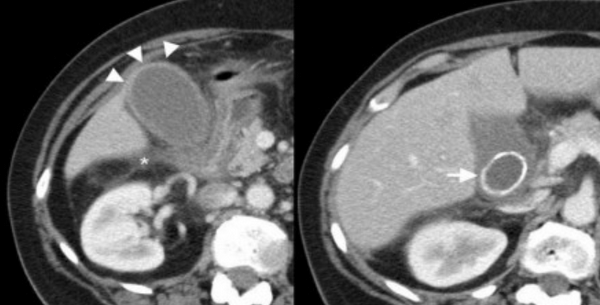

(Слева) На фотографии удаленного желчного пузыря внутри его значительно утолщенной стенки виден интрамуральный абсцессе. Часть печени, прилежащая к желчному пузырю, также была удалена, поскольку во время операции возникло подозрение на рак желчного пузыря. При патоморфологическом исследовании подтвердился ксантогранулематозный холецистит.

(Справа) На аксиальной КТ с контрастным усилением определяется утолщение стенки желчного пузыря, особенно выраженное в области его дна, граница между желчным пузырем и печенью нечеткая. Несмотря на то, что эти изменения подозрительны на рак желчного пузыря, при холецистэктомии был обнаружен ксантогранулематозный холецистит. (Слева) На аксиальной КТ у пациента с жалобами на боль в правом подреберье определяется неравномерное утолщение стенки желчного пузыря, выраженное в значительной степени; видны также несколько включений низкой плотности рядом с желчным пузырем и одно - в его стенке. Гиподенсные интрамуральные узлы при ксантогранулематозном холецистите могут представлять собой как абсцессы, так и ксантогранулемы.

(Справа) На аксиальной КТ без контрастного усиления у пациента с хронической болью в животе визуализируется увеличенный желчный пузырь с толстой стенкой, плохо отграниченный от паренхимы печени. Несмотря на то, что изменения не позволяют исключить рак, при оперативном вмешательстве подтвердился ксантогранулематозный холецистит.

(Слева) На аксиальной КТ с контрастным усилением у мужчины 75 лет без какой-либо симптоматики определяется иррегулярное утолщение стенки желчного пузыря с наличием в ней гиподенсных включений.

(Справа) На сонограмме у этого же пациента определяется асимметричное утолщение стенки желчного пузыря с наличием сладжа в его просвете и конкремента в области шейки. Визуализируется также участок неизмененной жировой ткани. Предоперационная дифференциальная диагностика рака желчного пузыря и ксантогранулематозного холецистита часто бывает сложной, однако отсутствие расширения желчных протоков позволяет предположить скорее хронический воспалительный процесс, а не новообразование.

о Возможно диффузное либо ограниченное утолщение стенки желчного пузыря в сочетании с нарушением ее дифференцировки:

о Наличие гиподенсных узлов и тяжей в стенке, представляющих собой участки инфильтрации пенистыми клетками, зоны некроза или абсцессы:

- Интрамуральные узлы могут занимать до 60% поверхности стенки

- Наиболее специфичные лучевые признаки КГХ

о Жидкость около желчного пузыря, воспалительные изменения, индурация, возможно, также свищевые ходы, абсцессы, ограниченная перфорация и др.:

- Воспалительные изменения могут захватывать прилежащие отделы печени, в результате чего граница между желчным пузырем и печенью становится нечеткой, что создает впечатление об инвазии рака желчного пузыря в печень